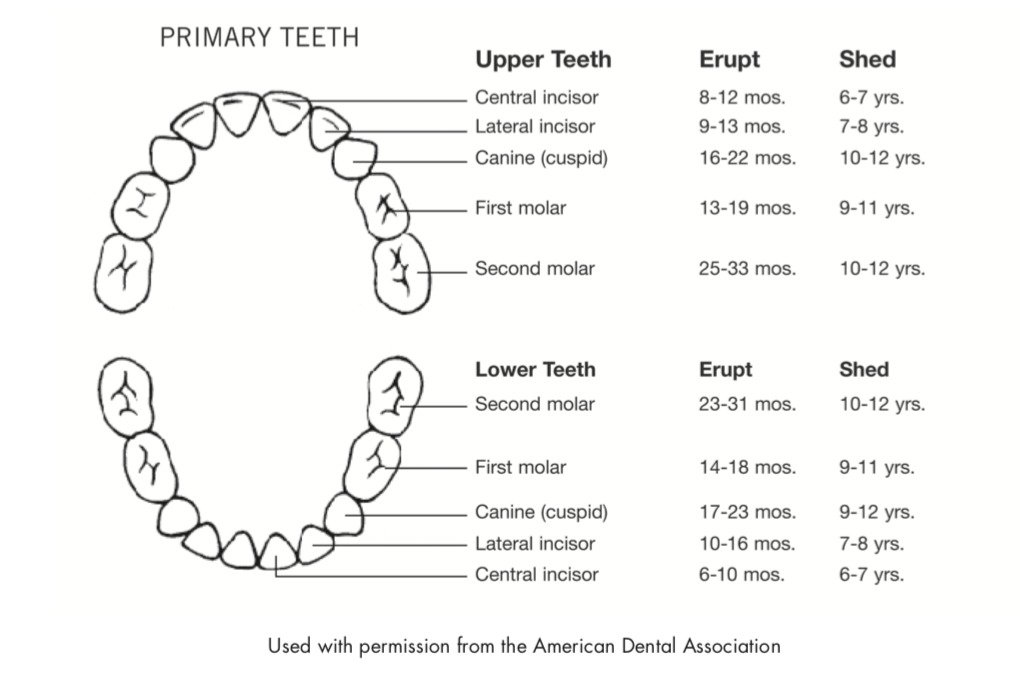

1.乳牙的生长顺序是什么?

通常第一颗乳牙萌芽在4-15个月期间。

有一个7+4的小规则,宝宝7个月的时候应该至少有一颗牙;到11个月的时候(4个月之后)应该至少有4颗牙;15个月的时候(4个月后),有8颗牙;以此以4的形式递增。

乳牙的成长顺序,中切牙(central incisors),侧切牙(lateral incisors),第一颗臼齿,牙尖(cannies), 第二颗臼齿。并不是所有宝宝是教科书般的顺序长牙的。

如果超过18个月,宝宝还没有长第一颗牙,需要看一下牙医。

宝宝的乳牙通常在3周岁的时候,会长满20颗。

一般牙齿脱落会从中切牙开始。

2.恒牙的生长顺序及生长参考时间

恒牙的生长期与乳牙相似,5-7岁开始生长,13-14岁结束。6岁的时候小朋友们会长出第一颗臼齿(molar)。

恒牙生长的顺序与乳牙相似,中切牙(central incisors),侧切牙(lateral incisors),第一颗臼齿,牙尖(cannies),第二颗臼齿,第三颗臼齿(智牙)。并不是所有宝宝是教科书般的顺序长牙的。

一般牙齿脱落会从中切牙开始。